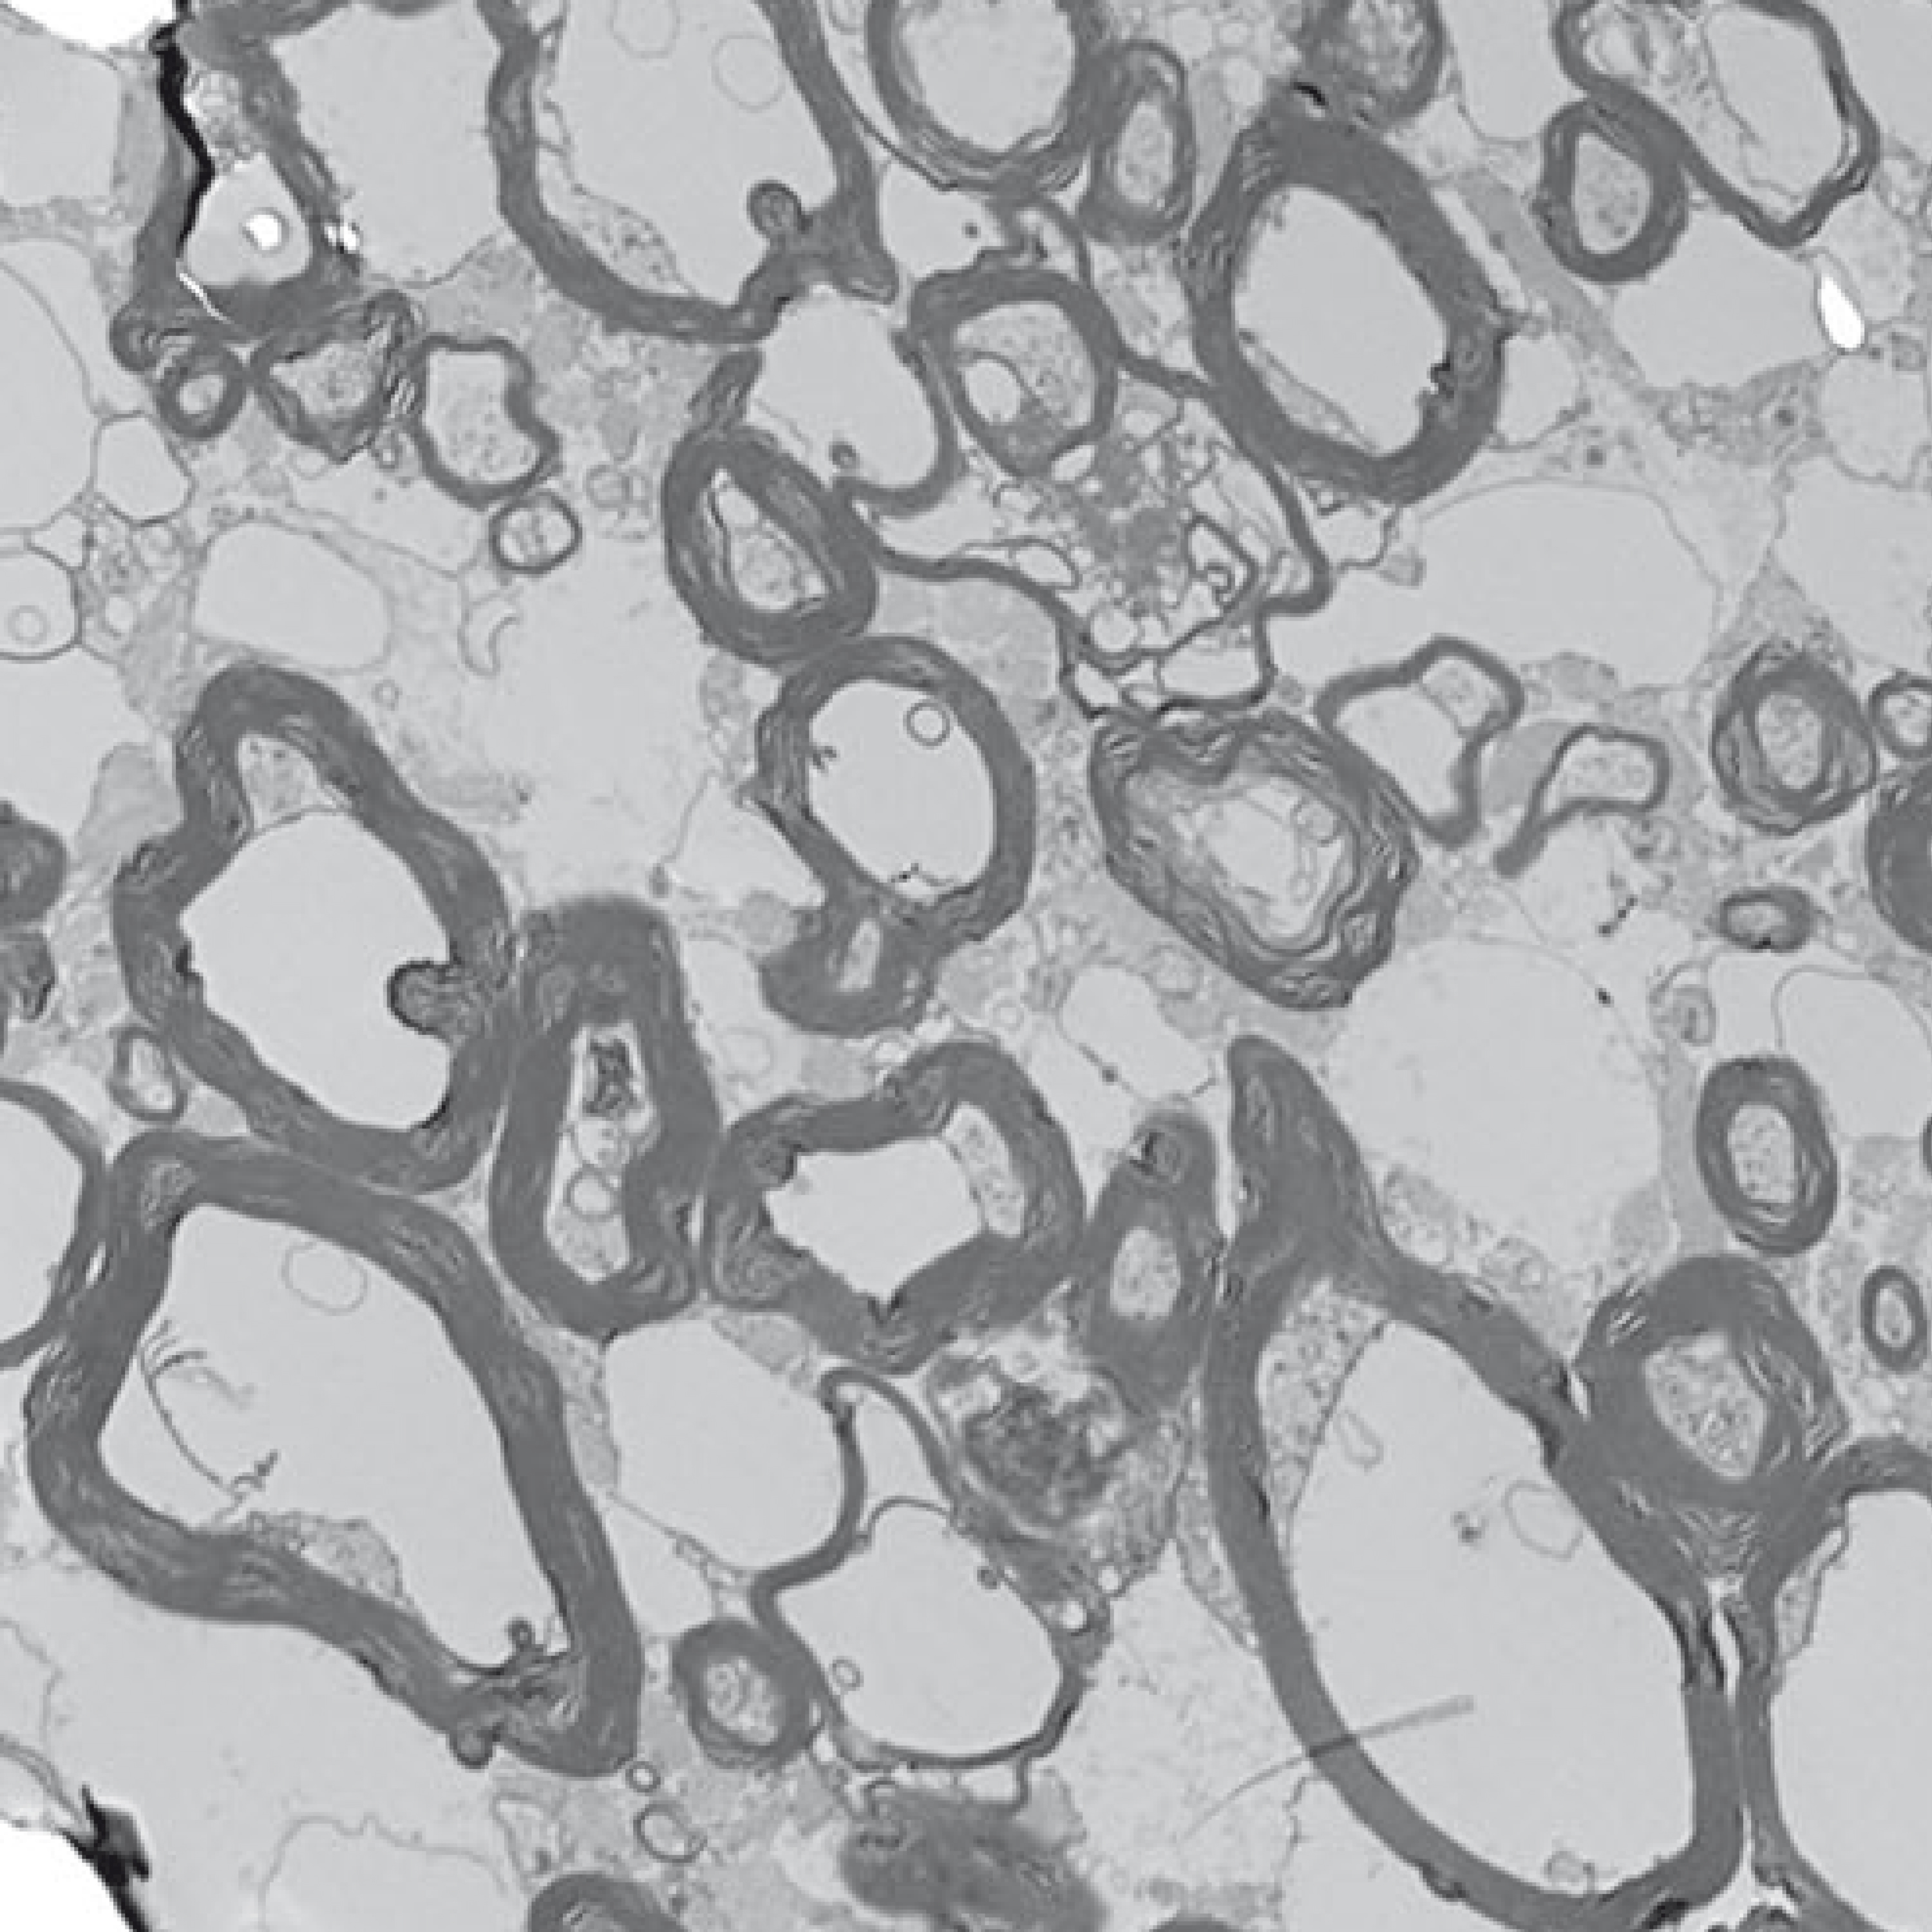

Postmortem Assessment of Olfactory Tissue Degeneration and Microvasculopathy in Patients With COVID-19

Interview with Cheng-Ying Ho, MD, PhD, author of Postmortem Assessment of Olfactory Tissue Degeneration and Microvasculopathy in Patients With COVID-1...